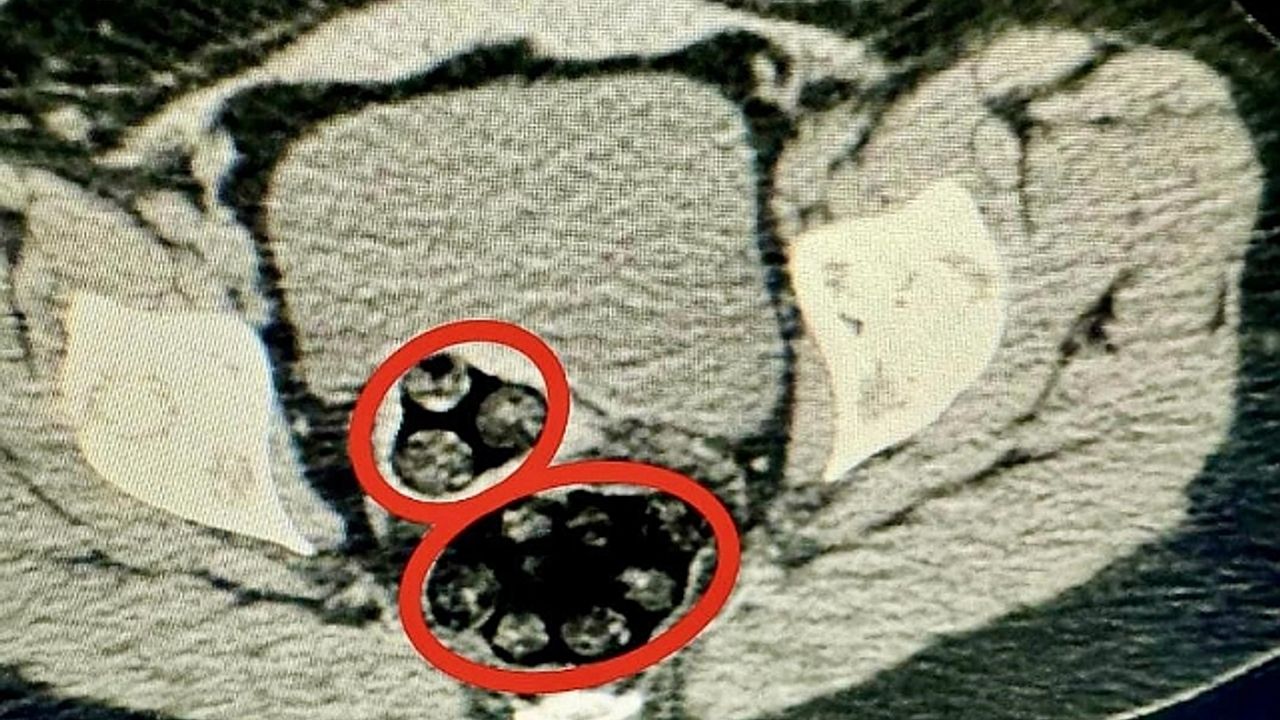

94 parça uyuşturucu cerrahi müdahale ile çıkarıldı

Otobüste gözaltına Fahımeh Golmohammadı Yenkejeh'in yapılan iç beden muayenesinde makadında cisim olduğu tespit edildi. Fahımeh Golmohammadı Yenkejeh'in makadına saklanmış bir şekilde 94 parça 550,63 gram metamfetamin uyuşturucu maddesi cerrahi müdahaleyle çıkarıldı.